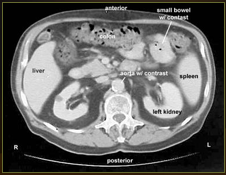

Computerized x-rays that produce cross-sectional images of the body layer by layer

What diagnostic tool?

CT scan aka CAT scan

Used to evaluate abdominal & pelvic organs

Imaged enhanced w/ IV iodine-containing contrast (water soluble)

Contrast usu. indicated

Common exception: Renal stone study

Which diagnostic tool?

CT scan

What type of diagnostic test is shown here?

CT abdomen with contrast